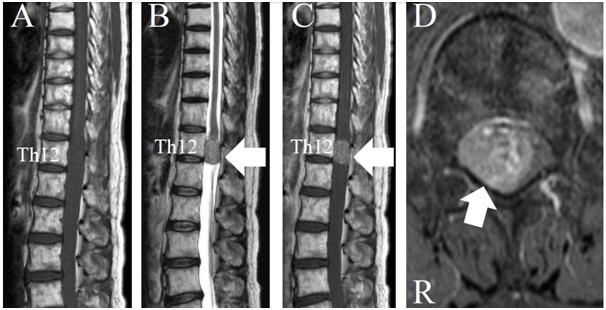

In 2015, a 62-year-old female presented to our hospital with gait disturbance and numbness in the bilateral lower extremities. There was a past history of adenocarcinoma in the apical portion of left lung that had been treated with chemotherapy and radiation in 2012 (Figure 1). In 2013, a brain metastatic tumor from lung cancer occurred that was treated with an operation and gamma knife.

Figure 1 Computed tomographic image of the chest. The tumor can be seen in the apex of the left lung (black arrow).